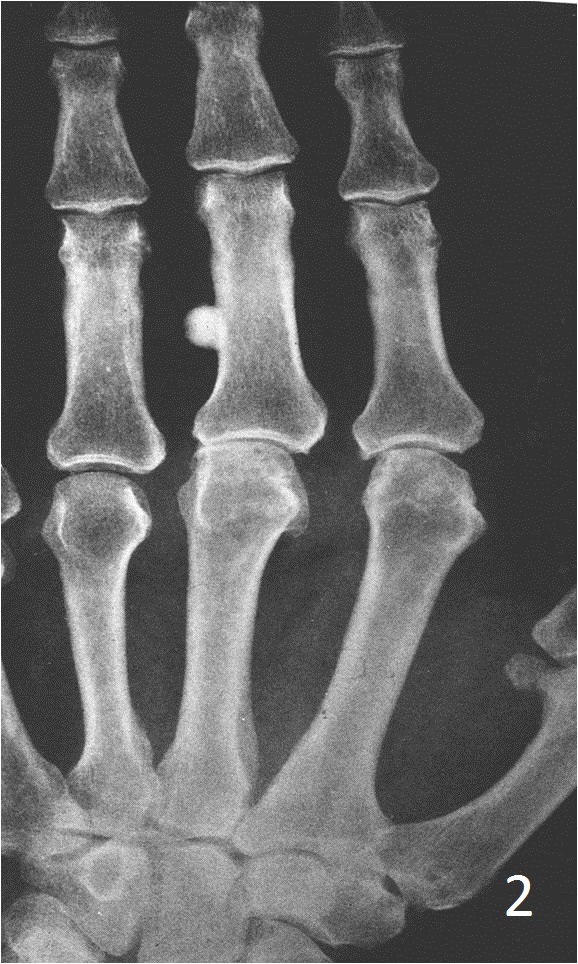

- Multiple osteomas/osteomas involving a long bone, rule out Gardner syndrome (osteomas, colon polyps and desmoid tumors)

Plain x-ray

- Sharply defined, radiopaque smooth, homogeneous bone protruding from the surface of a bone

- Almost appears as a localized thickening of the bone